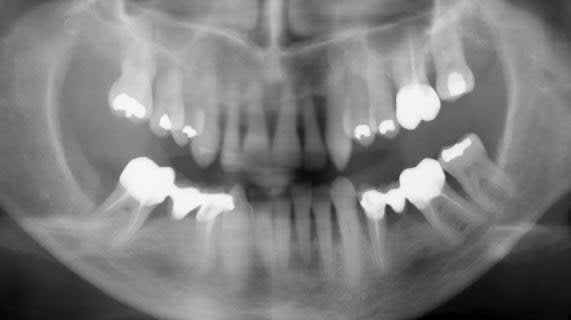

De 13 à 23, tu as beaucoup trop de perte osseuse pour faire de l'orthodontie. Le "trop tard" ne concernait pas l'âge de la patiente mais l'état de son parodonte.

Si je les ingresse, je vais de facto augmenter leur support osseux, non ?

Tu penses vraiment que ce n'est pas possible ?

Le truc, c'est que les pbs paro sont généralisés et qu'en faisant l'ingression des dents, y a 9 chances sur 10 que tu n'obtiennes...que des poches paro plus profondes...

Comment espères-tu retrouver une attache alors que tu a perdu depuis belle lurette la zone cellulaire du cément sur 75% de la racine?

En admettant que tu arrives à ingresser, je crains que tu ne crées de la cratérisation...